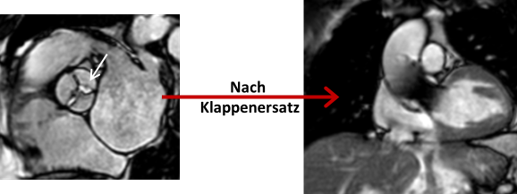

3. Strukturelle Herzerkankungen (SHD) und angeborene Herzfehler

Mit Hilfe von planimetrischen Verfahren (Bestimmung der Klappenöffnungsfläche) sowie Phasen-Kontrast-Sequenzen kann sowohl die morphologische als auch funktionelle Quantifizierung von Herzklappenerkrankungen (z.B. Aortenklappen-Erkrankungen) erfolgen. Nach erfolgter minimalinvasiver Klappenimplantation kann die Funktion der Herzklappe sowie die Struktur des Myokards verlaufsbeurteilt werden.

Vor und nach Aortenklappenersatz Darstellung großer Gefäße